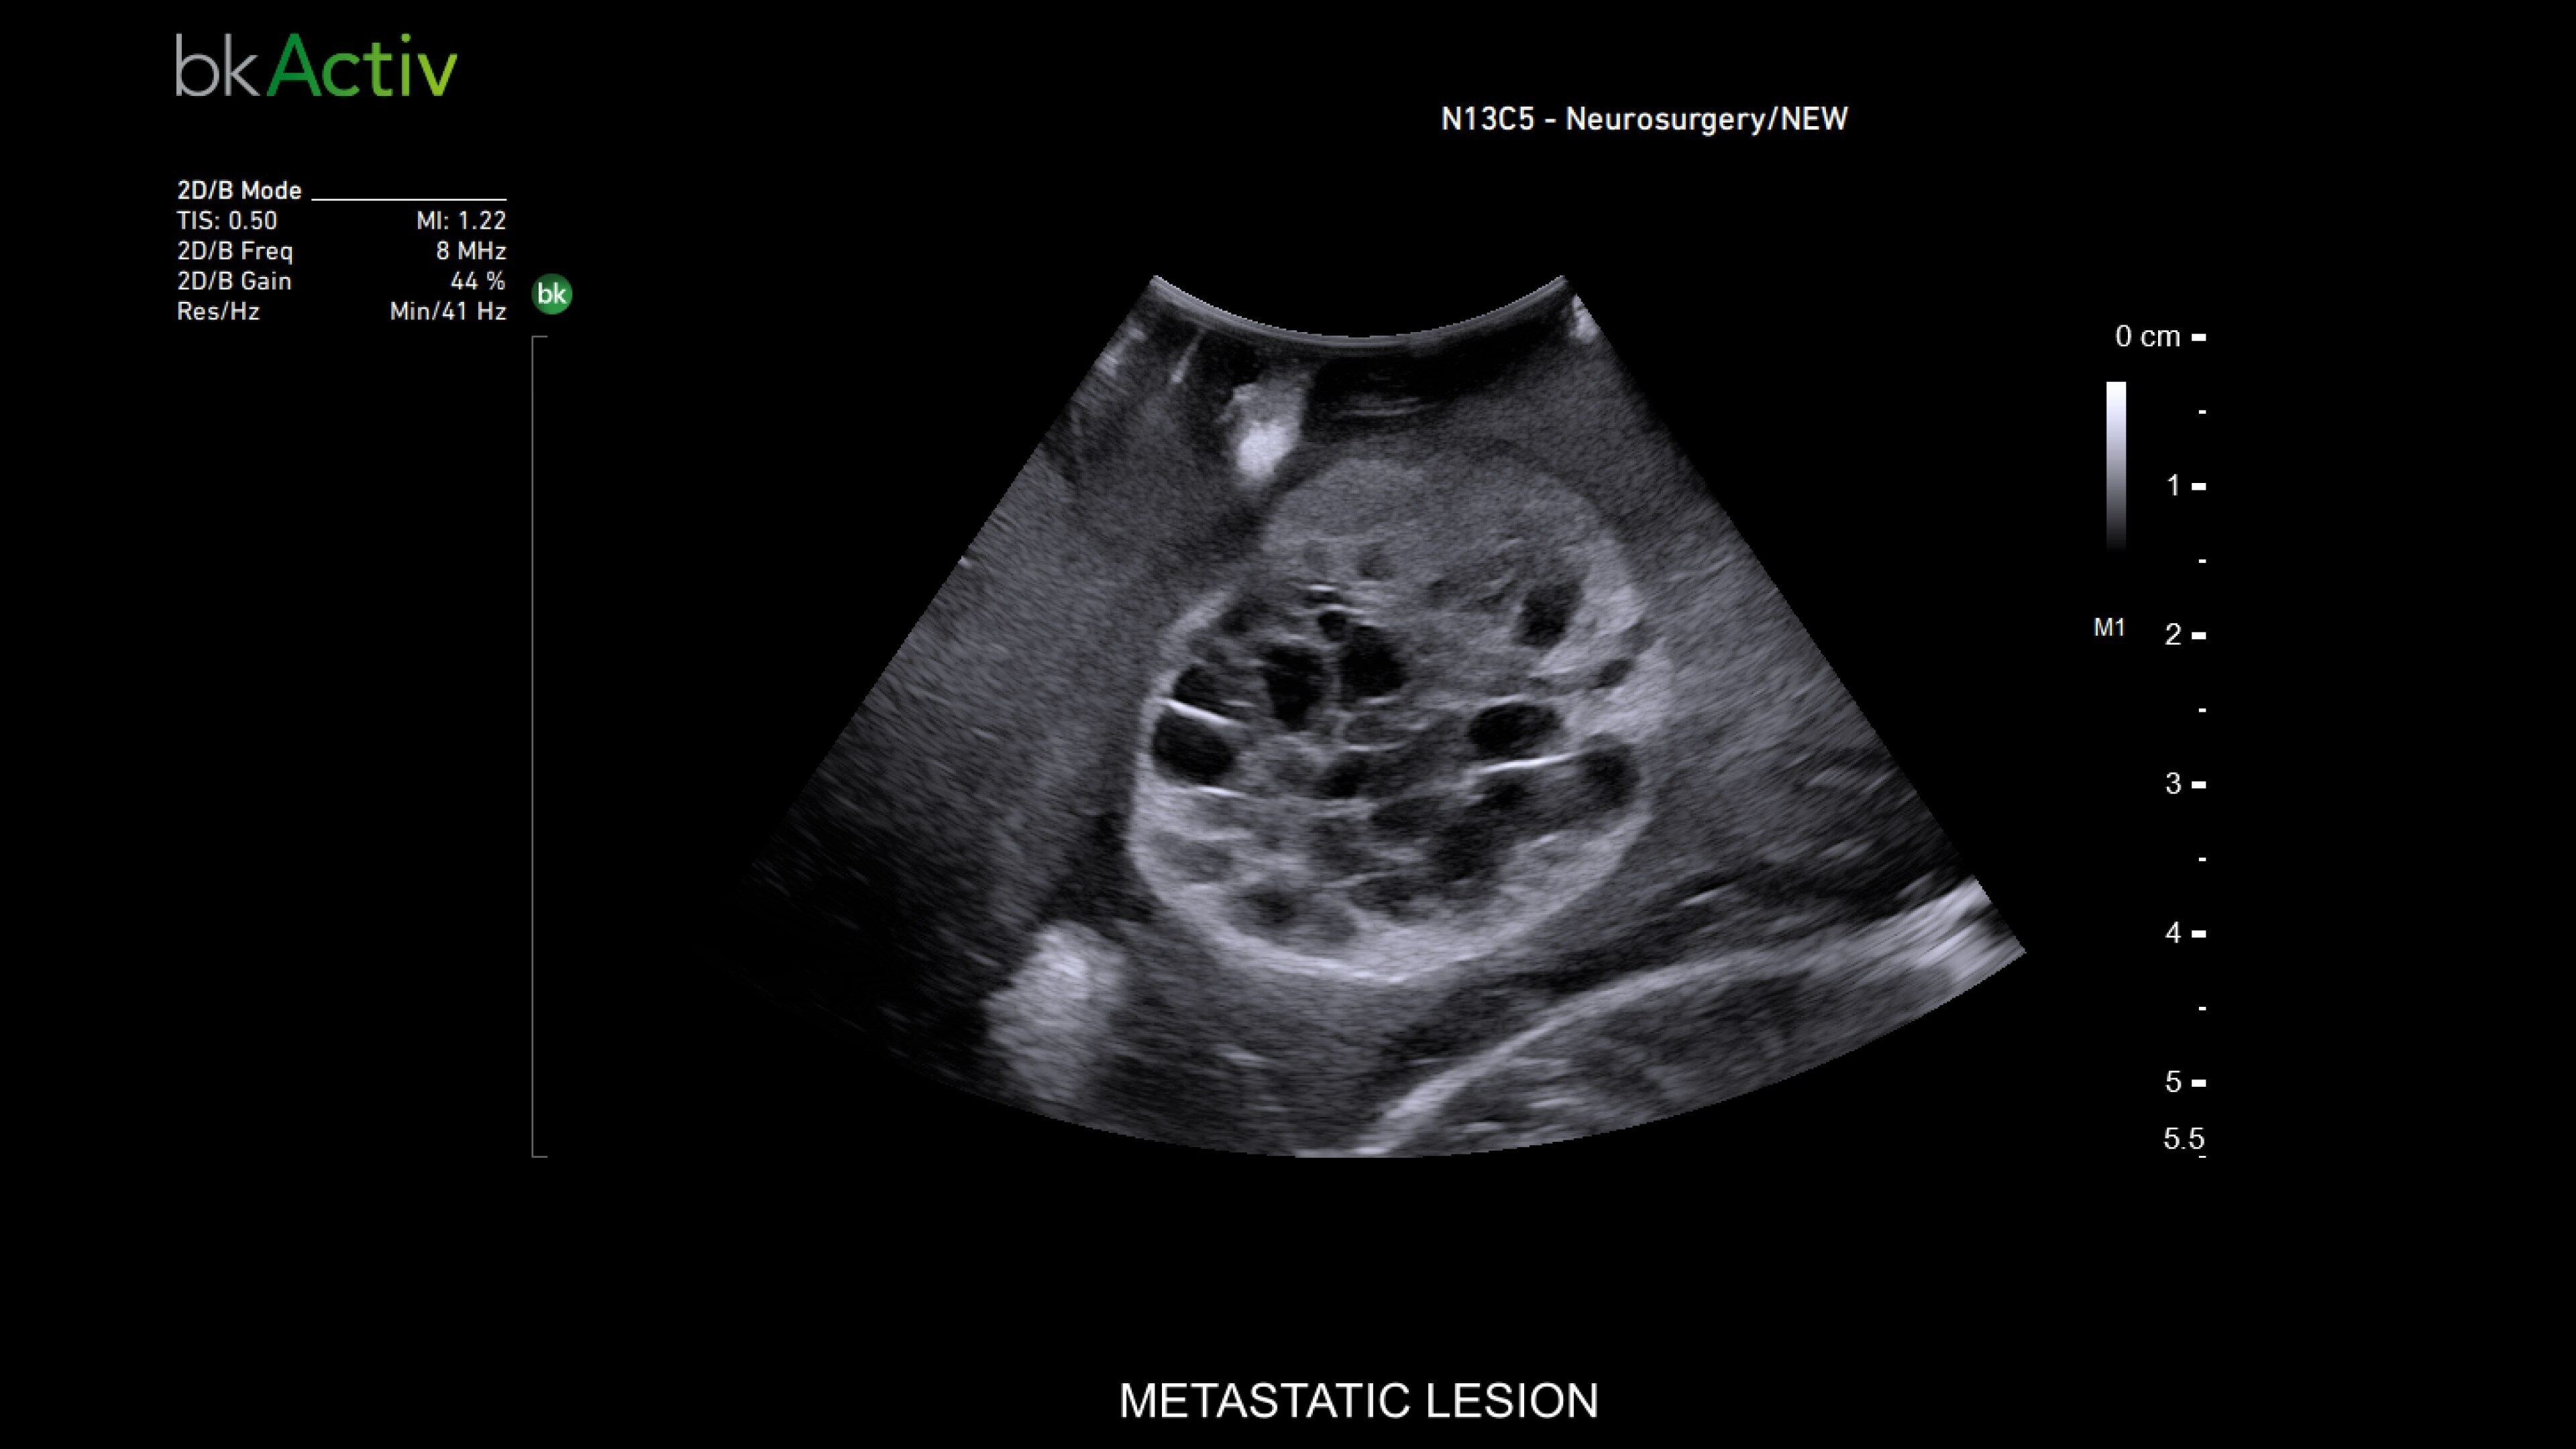

Neurosurgery and spine

Advanced imaging for neurosurgery

The bkActiv ultrasound system provides real-time imaging for neurosurgery and spine procedures. Its improved algorithms offer uniform image resolution, greater detail around lesion borders, and enhanced penetration. The system includes specialized transducers, such as the N13C5 craniotomy transducer for deep penetration and the N20P6 minimally invasive transducer* for accessing hard-to-reach areas. The Smart Button™ technology allows neurosurgeons to control images within the sterile field, ensuring precision during complex procedures.